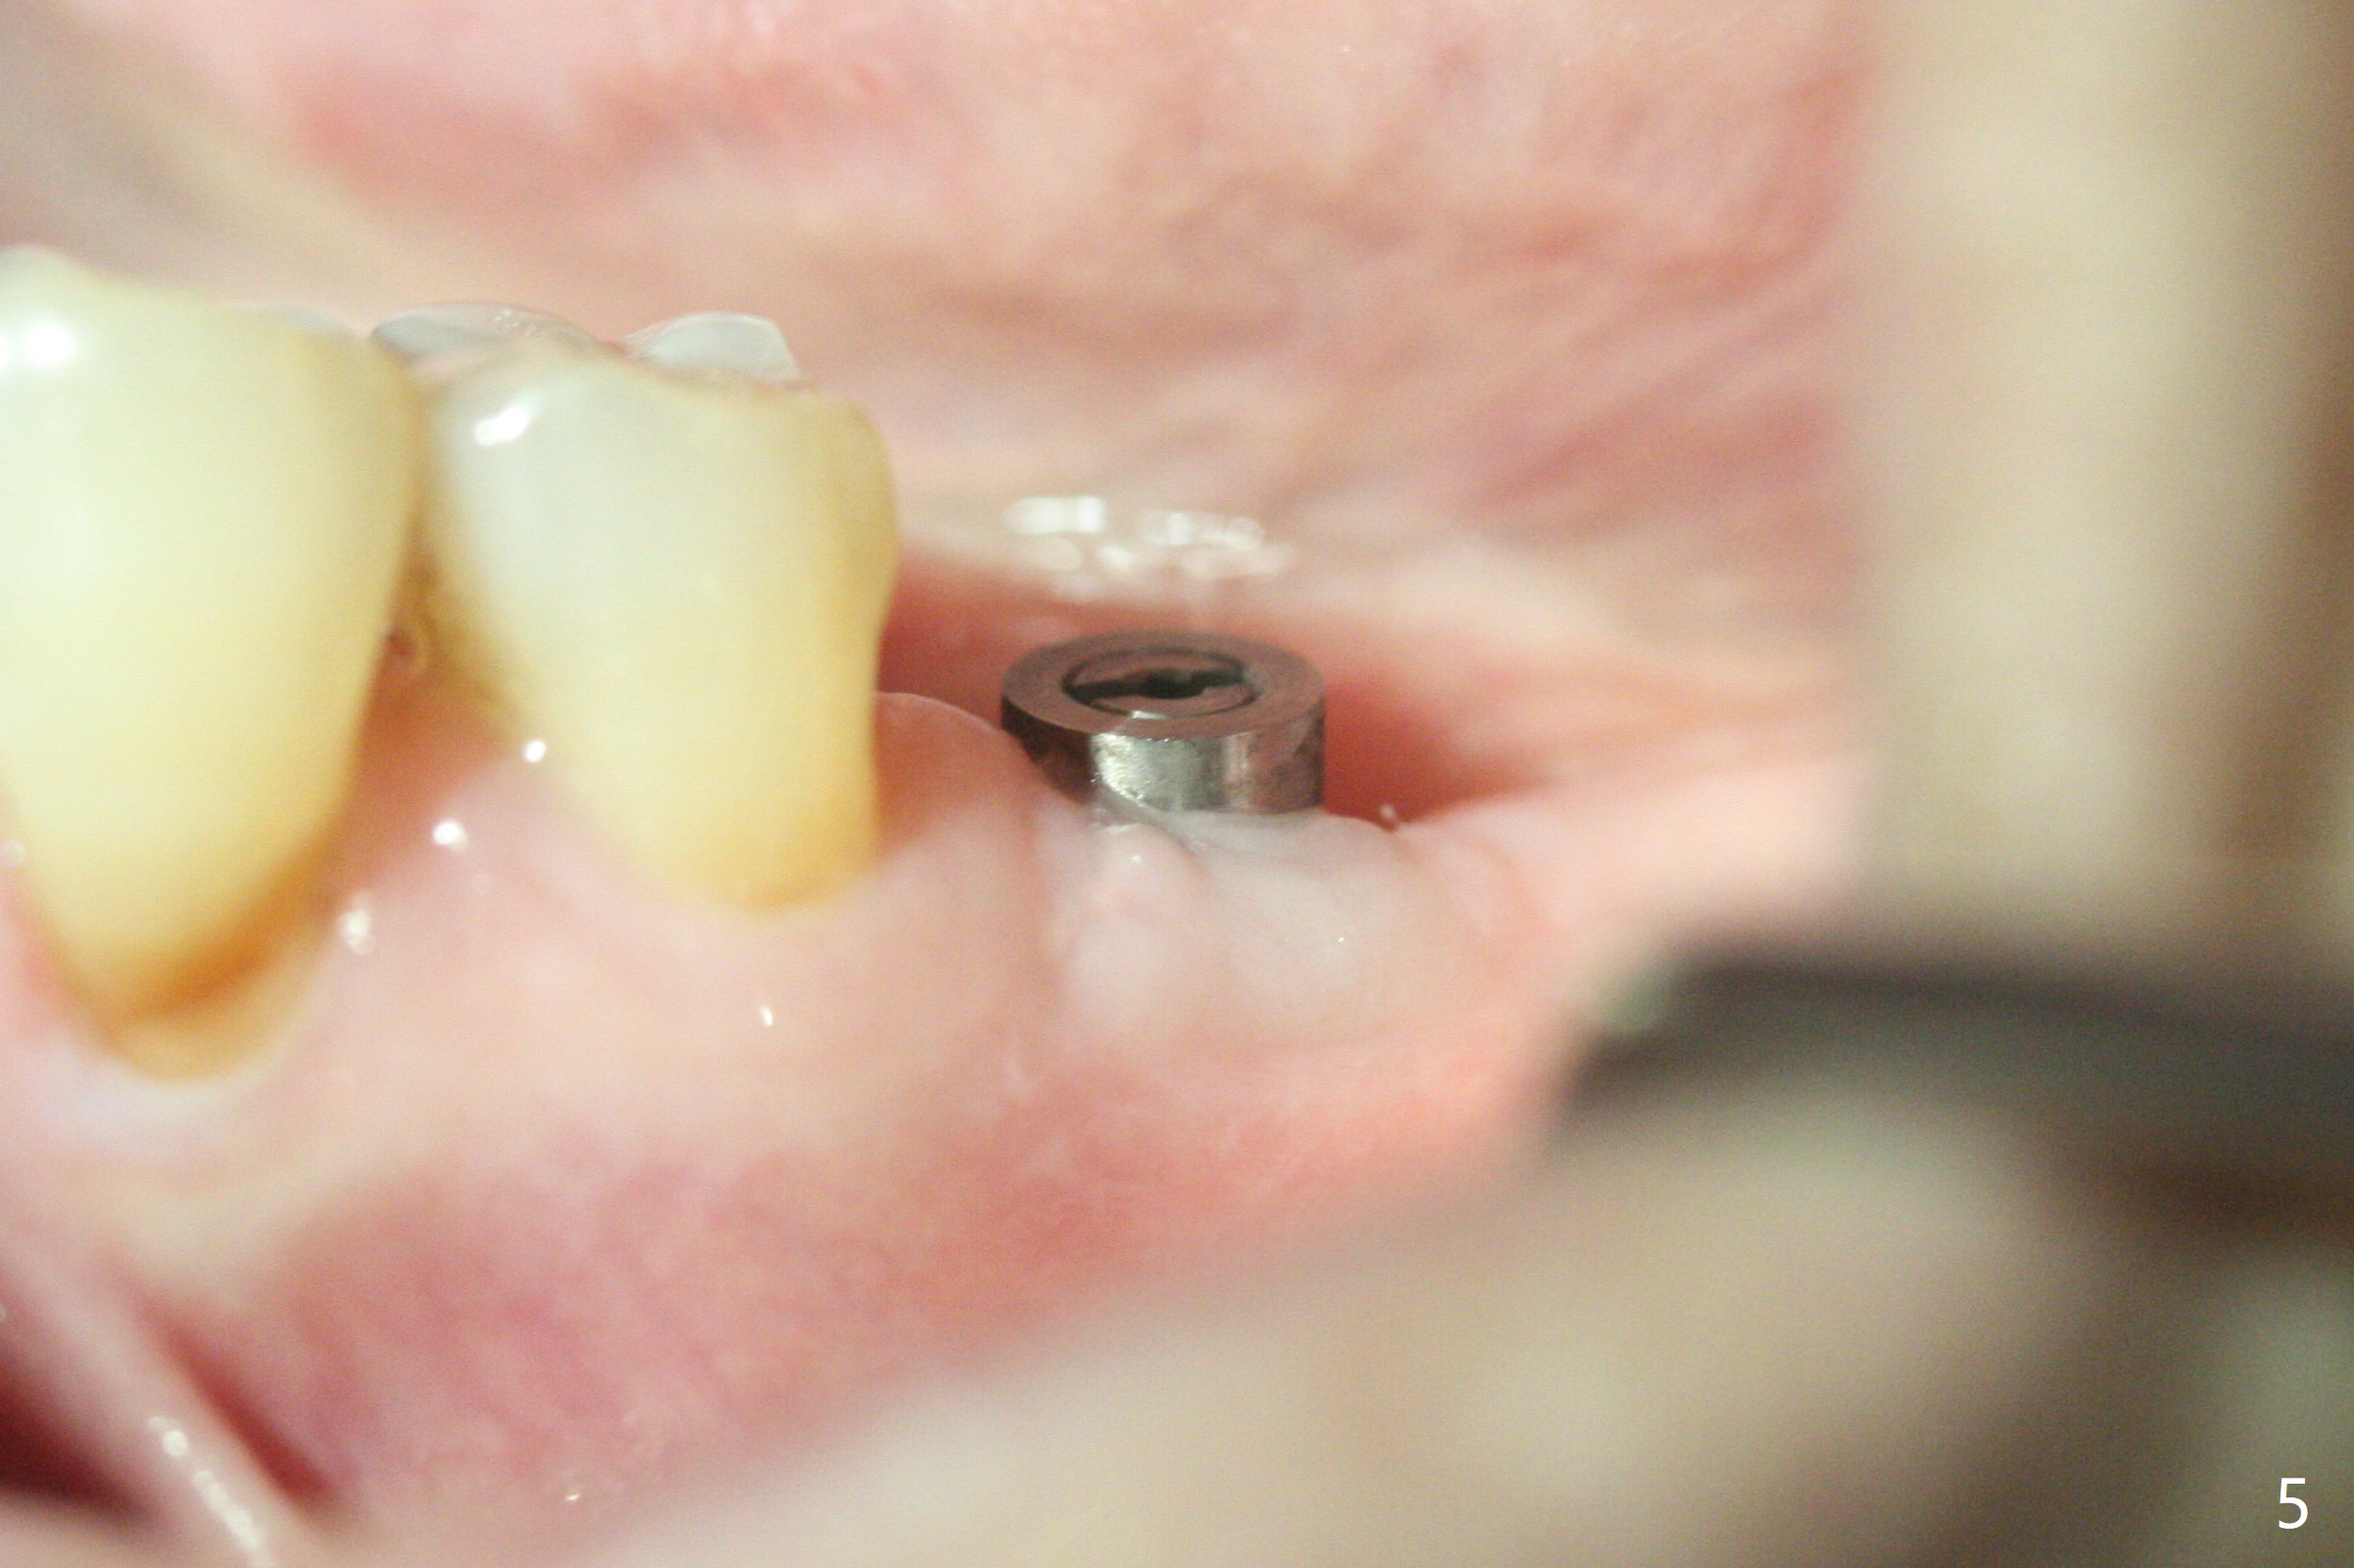

Following light use of 4 mm tissue punch, a buccal incision is made and raised. After 4x8.5 mm drill with 10.5 mm offset at #19, 4.5 mm cortical drill is used for 2/3 length to take care of the thick dense lingual plate (overprep). The remaining apical 3 mm osteotomy is underdrill (3.5 mm). After try-in of a 4.5x14 mm tissue-level dummy implant, a same-sized definitive one obtains 35 Ncm torque (Fig.1). Following 3-4 more turns, the torque reaches 45 Ncm (Fig.2) with the distal thread covered (<) and autogenous bone graft placed in the distal defect (*). A 4x3 mm unipost is placed to keep periodontal dressing in place. Clinically the implant is placed within bone boundary buccolingually. The new implant seems necessary considering short (Fig.2 S) and probably resorbed (Fig.1 R) roots of the premolars. In fact the short abutment keeps the mesiolingual portion of periodontal dressing for 2 weeks; since local hygiene is suboptimal, the healing screw is placed after abutment and dressing removal (Fig.3).